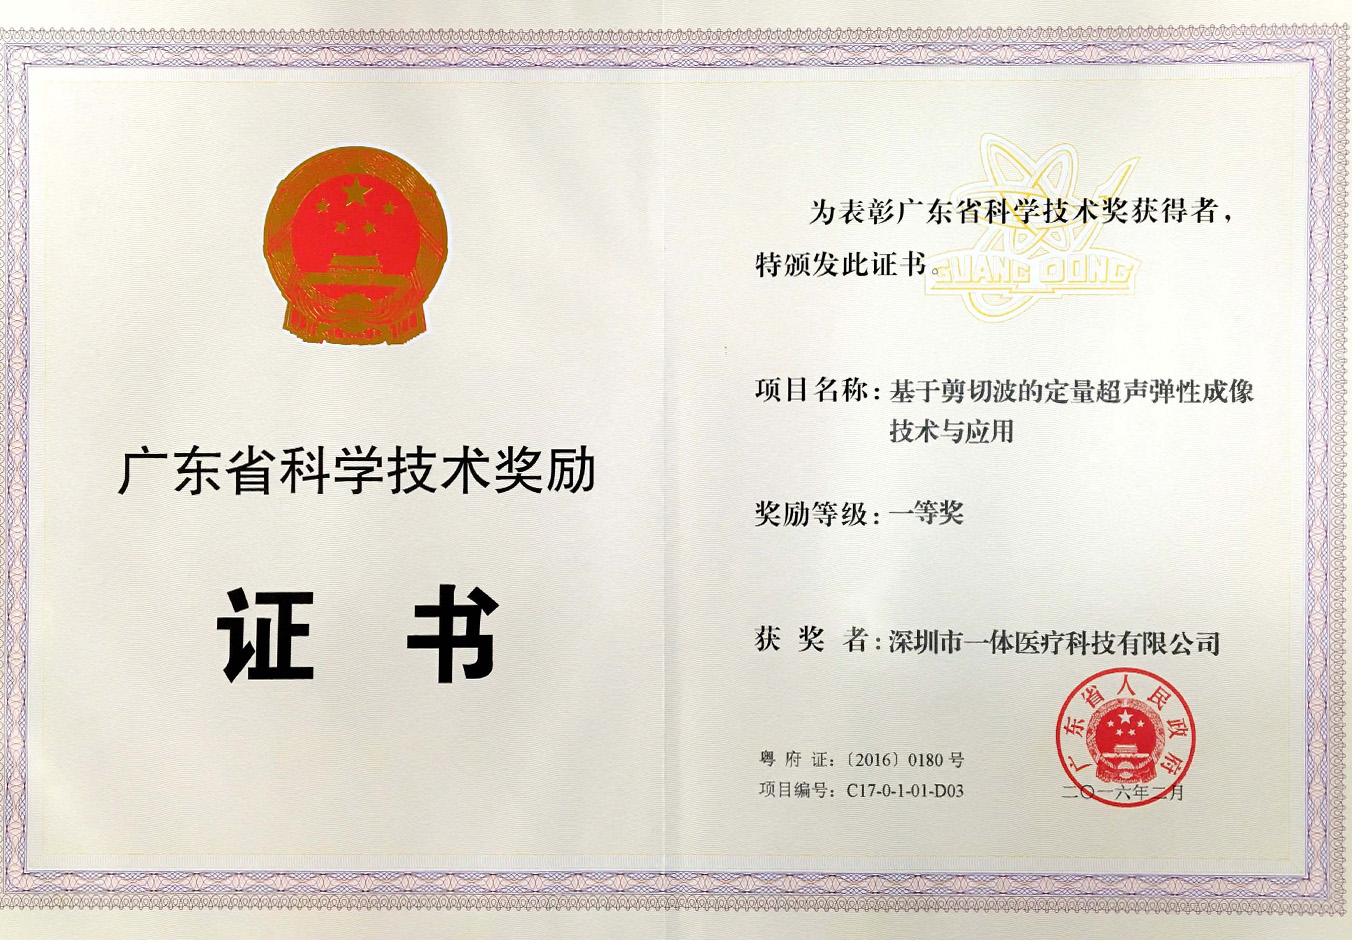

е№ҝдёңзңҒ科еӯҰеүҚиҝӣдёҖзӯүеҘ–